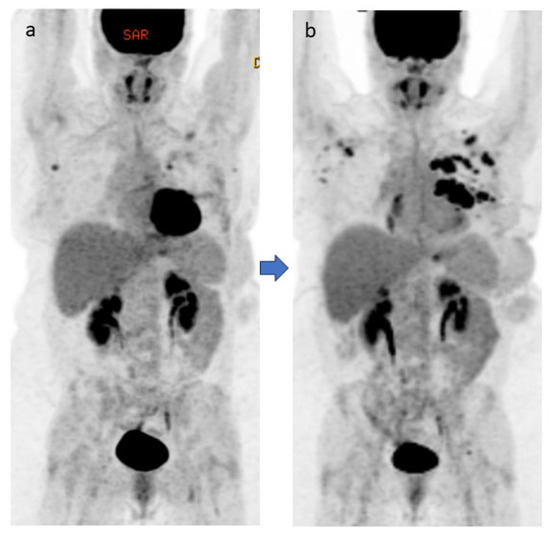

4.1. Case #1

4.2. Case #2